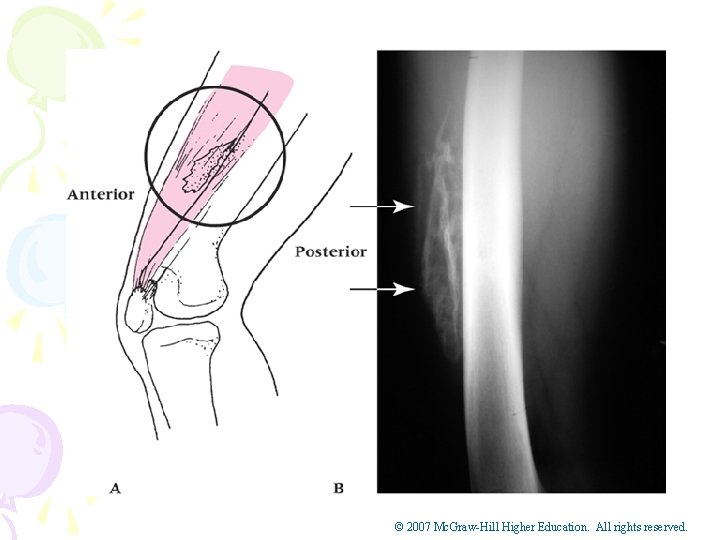

• Myositis Ossificans – Cause of Injury • _________________ – Signs of Injury • _________________ • Pain, weakness, swelling, decreased ROM • Tissue tension and point tenderness – Care • Treatment must be conservative • May require _________ if too painful and restricts motion • If condition is recurrent it may indicate problem with blood clotting © 2007 Mc. Graw-Hill Higher Education. All rights reserved.